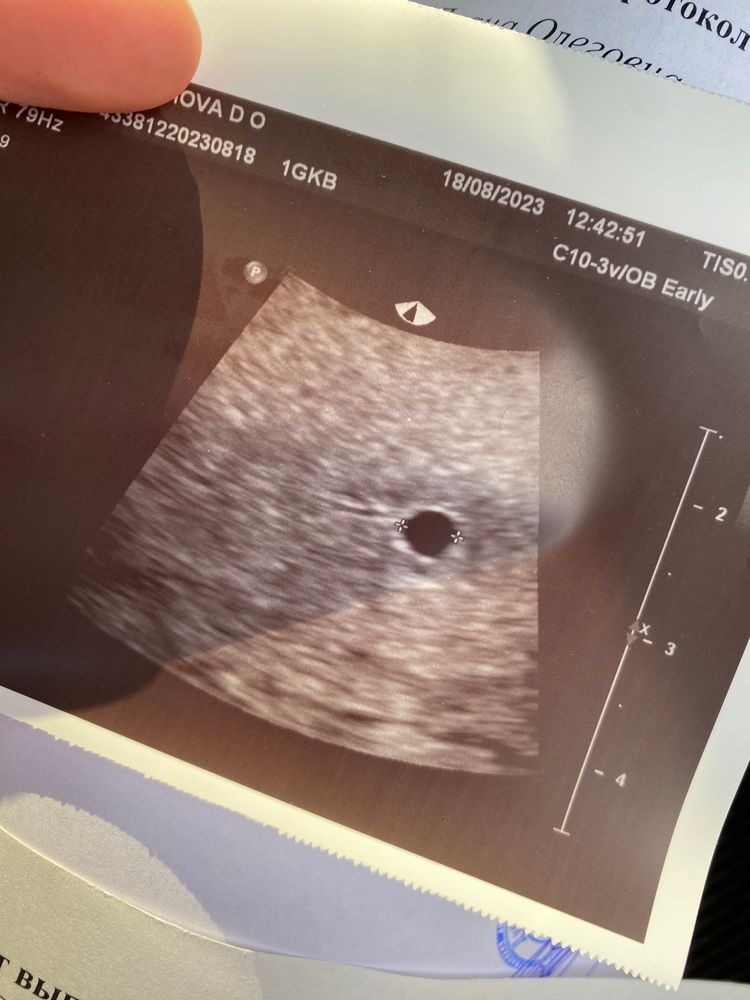

Первое УЗИ

Сходила сегодня на УЗИ. По мес срок 5н6д. Так рано шла только для того, чтобы подтвердили МАТОЧНУЮ беременность. Подтвердили 😅

И подтвердили мои предположения о поздней овуляции. Срок по УЗИ поставили 5н1д.

Желтое тело 22мм в правом яичнике

Плодное яйцо 4,2мм

Эндометрий 11,6мм

Прикрепление в верхней трети матки.

Через 2 недели можно повторить УЗИ, что бы увидеть эмбрион и СБ)